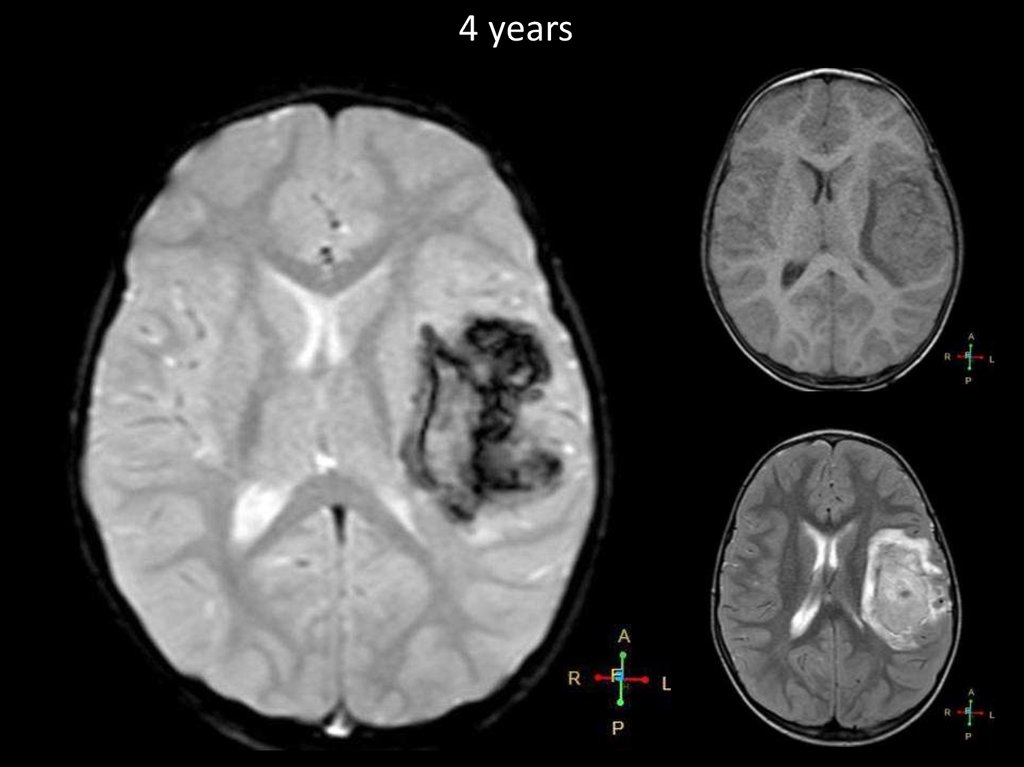

4 years

9.